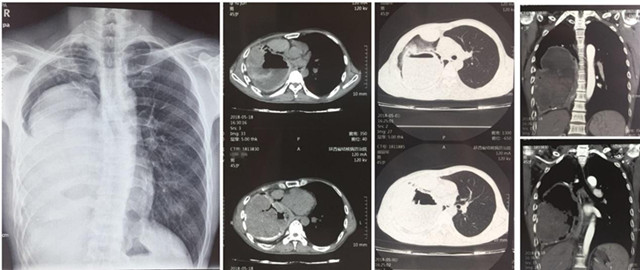

来自渭南澄县的45岁黄某患上了一种奇怪的病,10年前,他无明显诱因出现咳血伴有头晕和乏力,当时由于咳血量小,加之家庭经济条件差并未重视,只要出现该症状都自行购买药物治疗,近5年来咳血频次明显增加,每次咳血量达100ml以上,家人带着他辗转咸阳、西安多家医院,均考虑为肺结核伴脓胸,给予抗痨治疗,但无法有效控制反复出现的咳血症状,眼看黄某身体状况每况愈下,家人心急如焚。5月15日,家人携患者抱着最后一线希望来到香港正牌挂牌之综合挂牌外科,接诊的陈其亮主任医师和李军孝副主任医师对他进行了详细快速的检查,发现患者血压只有90/60mmHg,血色素75g,医生紧急给患者纠正贫血预防休克治疗后,进一步检查发现患者右侧胸腔内可见一罕见的巨大包块,占据80%的胸腔,包块内密度不均匀,右上胸腔仅有的肺组织也呈蜂窝病变结构。让人不解的是,患者既然被我省多家医院诊断为“结核性脓胸”,但从我院诊查后来看,无论是影像形态、生化检查,还是病原病检均无结核感染依据;而且伴随长期咳血的源头是否和占位灶及其滋养血管有关不得而知。目前治疗的唯一手段就是手术,但盲目手术,则是雪上加霜,死亡风险极大。陈其亮科主任及李军孝副主任在科内对患者病情进行详细的讨论和分析后,考虑患者最大的可能是肺源性支气管囊肿并混合感染。由于胸内占位病灶滋养血管丰富,走形错综复杂,压力较大,若不及时控制,患者随时有大咳血至休克死亡的可能。时逢我院承办首届“一带一路”结核病长安论坛之际,陈其亮主任特邀参会嘉宾复旦大学公卫中心胸外科宋言峥主任、山东胸科医院胸外科金锋与影像科候代伦主任为患者会诊,经过论证认为我院外科的针对该病的手术方案(胸膜全肺切除术)指征明确,具有可实施性。

经过精心而充分的准备,陈其亮主任、李军孝科副主任、崔渊博主治医师和麻醉科王君毅医师等按照拟定的手术方案,于5月28日晨8时准时时开始,术中果然出现术前所预料的胸腔创面渗血,肺门粘连及血管畸变等问题,随着手术的推进,患者血压持续偏低(90-60/50-30mmHg),但这些都被我们术前制定的术中紧急应对预案一一化解,经过约4小时50分钟顺利完成胸膜全肺切除,术中共输血3200ml,术后生命体征平稳,术后病理回报印证了术前的诊断。截止目前患者恢复良好,再未出现咳血等呼吸道不适症状,血色素已恢复正常,患者转危为安,家人激动的说:“这么多年的病搞清了,也治愈了”。